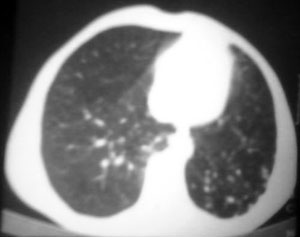

以下是引用逸风在2006-9-12 14:57:00的发言:[br]ct显示双肺上叶点片状及纤维索条状密度不均影,肺野外带近胸膜可见大小不等的含气空腔,壁略厚,境界清晰,未见液平面,中下肺野散在小片状及点状高密度影;纵隔内显示点状钙化,未见明显淋巴结肿大,构成胸廓诸骨未见明显异常.[br]诊断意见:1.双肺结核合并支气管播散;2.双肺上肺大泡.